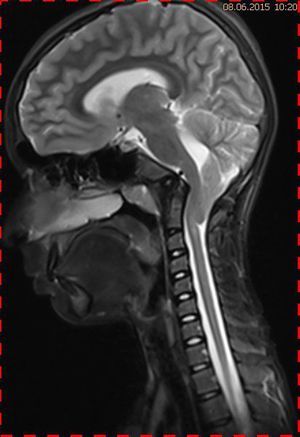

Abb. 4.1 MRT (T2 TSE, 1,5 T) sagittal: Kompression des Kleinhirns durch ein großes Tentoriummeningeom (Pfeil) mit Verlagerung der Tonsillen in das Foramen magnum

Abb. 4.2 MRT (T2 TSE, 1,5 T) sagittal: Kontrolle nach 1 Jahr, Ausschluss Tumorrezidiv, normale Position der Kleinhirntonsillen

Abb. 4.3 MRT (T2 TSE, 1,5 T) sagittal: postoperativer infratentorieller Substanzdefekt nach Entfernung des Meningeoms und nuchale Suszeptibilitätsartefakte; Retraktion der Tonsillen in die hintere Schädelgrube

Natürlich kann eine Dislokation der Kleinhirntonsillen in das Foramen magnum auch andere Ursachen haben, wie das Fallbeispiel 2 zeigt (Abb. 4.1 bis 4.3). Eine 57-jährige Patientin hatte ein monströses Tentoriummeningeom entwickelt, das zu einer Verlagerung der Kleinhirntonsillen nach kaudal führte. Die postoperativen Verlaufskontrollen zeigten die Repositionierung der Tonsillen in der hinteren Schädelgrube.